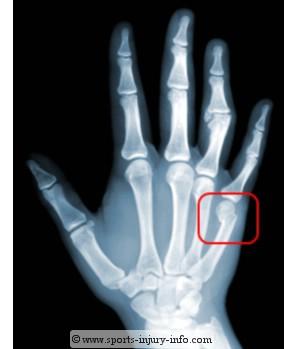

426